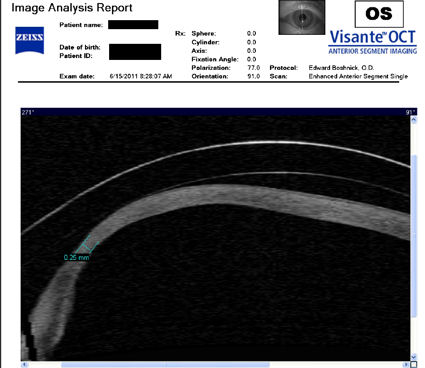

Следующие изображения были получены с использованием метода, называемого оптической когерентной томографией, или ОКТ. Прибор позволяет получить изображение в поперечном сечении путем сканирования передней части глаза (переднего сегмента) лучом света. Думайте об этом как об ультразвуке, использующем свет вместо звуковых волн для создания изображения живых тканей.

На изображении ниже представлен снимок роговицы в поперечном сечении после операции LASIK. Белая изогнутая линия вверху - это передняя поверхность твердой контактной линзы. Следующая едва заметная белая линия - это задняя поверхность линзы. Следующая область, которая имеет зернистый вид, - это пространство между хрусталиком и роговицей, заполненное физиологическим раствором. Роговица имеет классические признаки эктазии - истончение, выпуклость и неправильную форму.

На снимке ниже показана роговица пациента, у которого после операции LASIK развилась эктазия. Пациент носит жесткие склеральные контактные линзы. Вы можете видеть выпячивание роговицы в самом слабом месте (эктазия), что приводит к сильному искажению зрения. Очки и мягкие контактные линзы неэффективны для таких глаз, как этот. Нажмите на изображение, чтобы увеличить.

У пациентки, описанной ниже, развилась эктазия роговицы после операции LASIK, и ее лечили с помощью ПОТРЕБЛЯЕМЫЕ ВЕЩЕСТВА . Противоположные красные стрелки указывают на переднюю и заднюю поверхности склеральной линзы, которую носит пациент. Зеленая стрелка указывает на заполненное жидкостью пространство между линзой и роговицей. Белая стрелка указывает на заднюю поверхность лоскута LASIK, который никогда не заживает. Синие стрелки указывают на два INTAC, которые имплантированы в роговицу. Тот факт, что пациент сейчас носит склеральные линзы, указывает на то, что имплантация INTAC не привела к восстановлению функционального зрения. Нажмите на изображение, чтобы увеличить.

Изображения любезно предоставлены доктором Эдвардом Бошником, который посвятил свою практику восстановлению качественного зрения и информации о эктазия после операции LASIK .